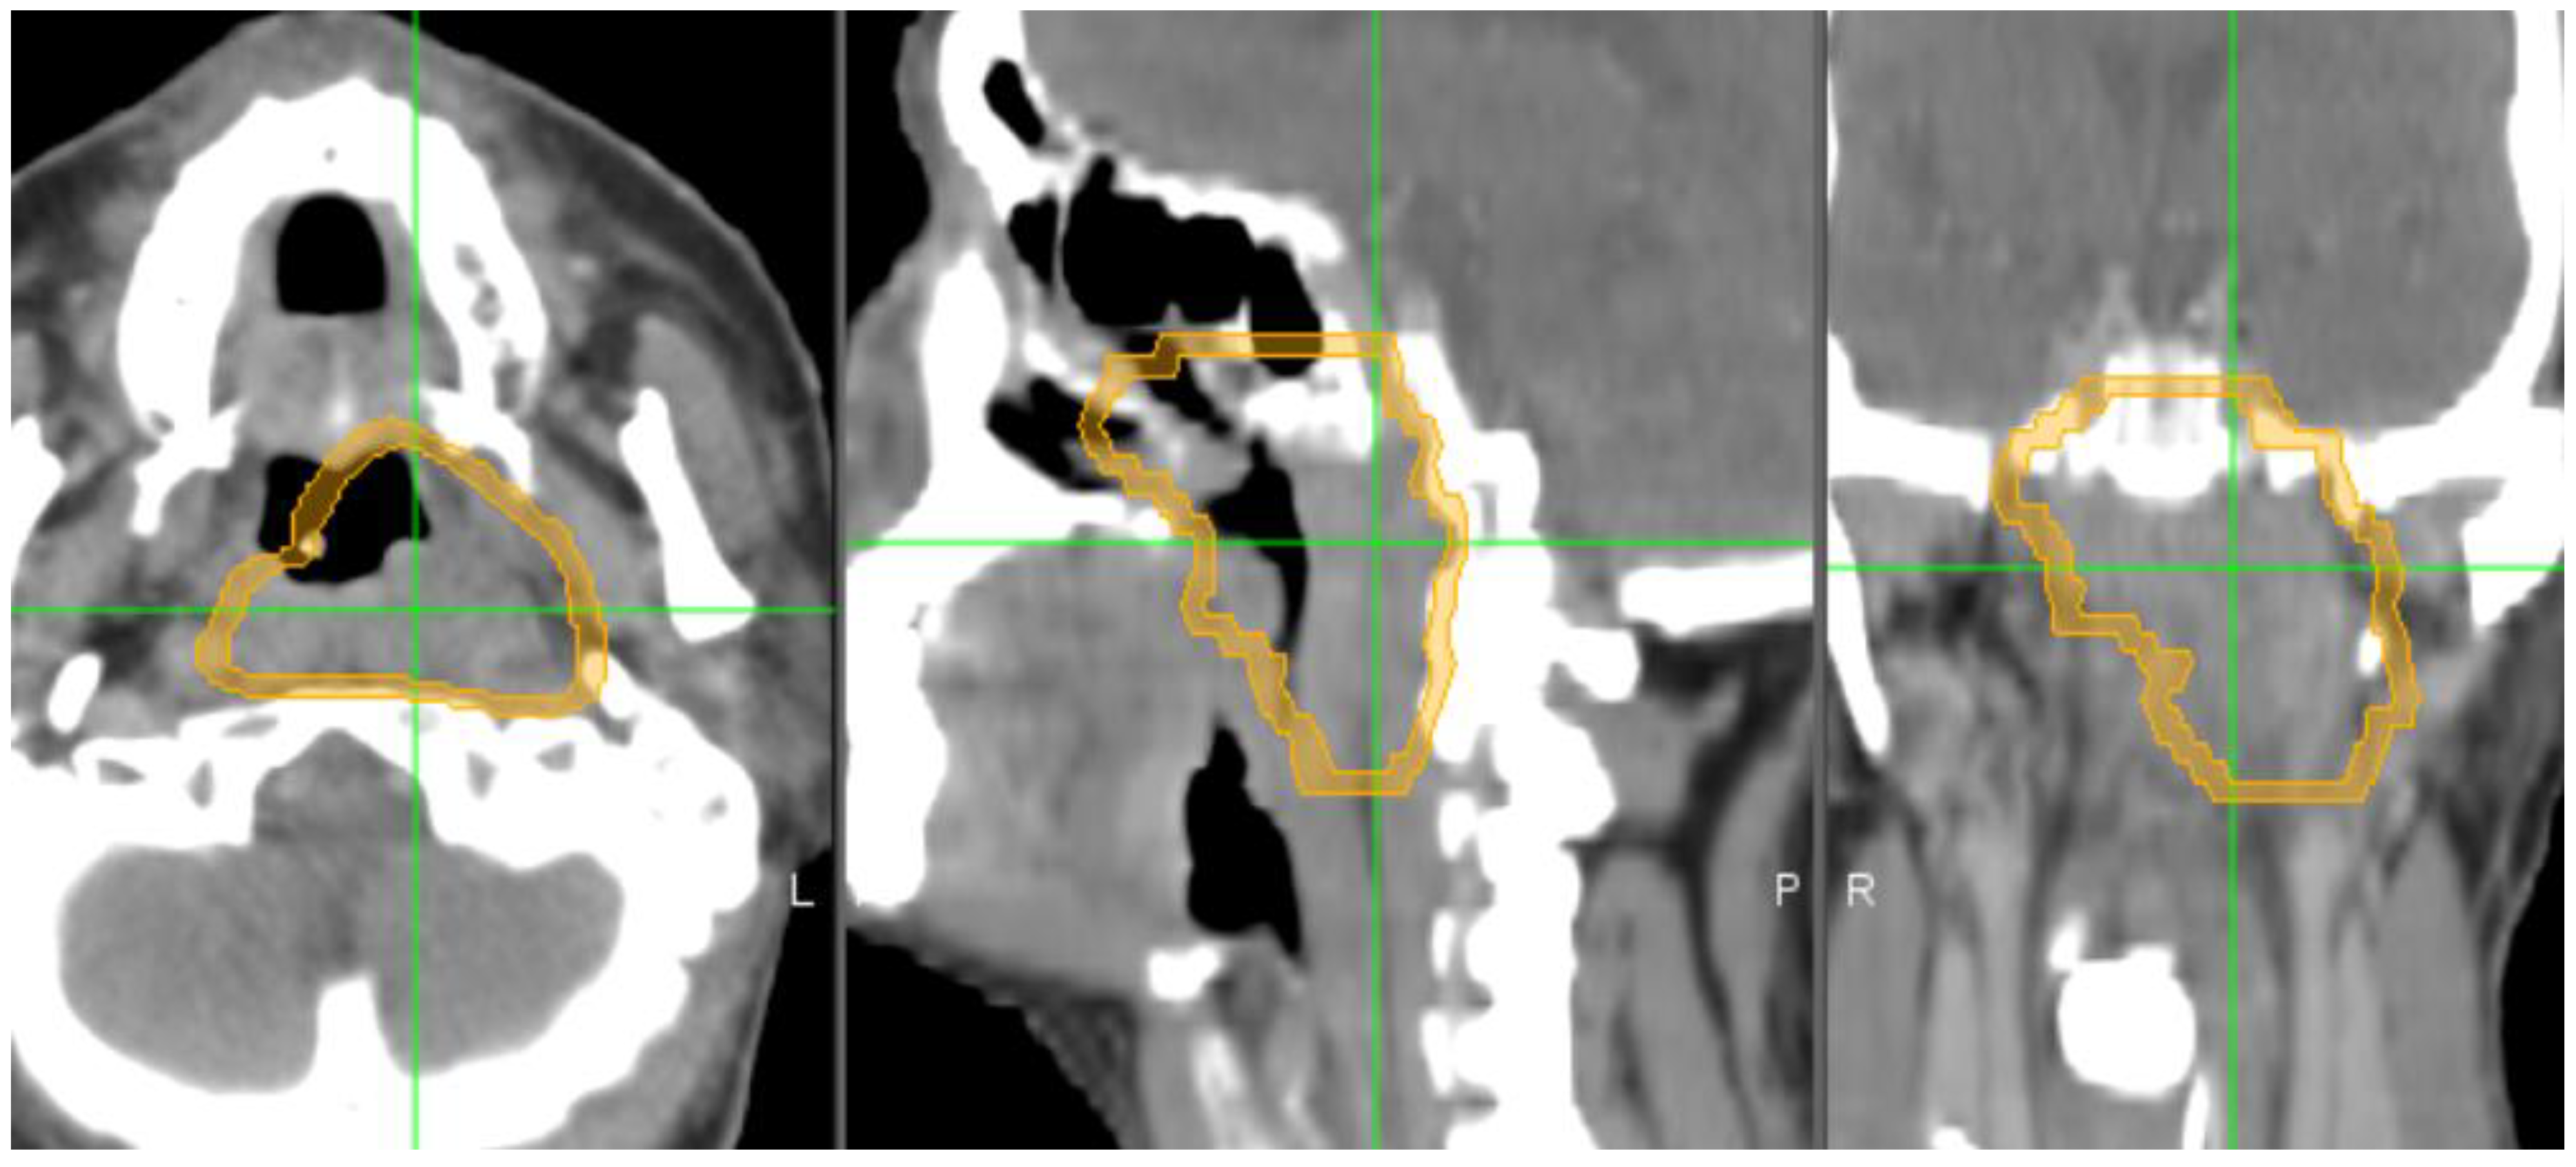

2.2. Target Delineation and Segmentation